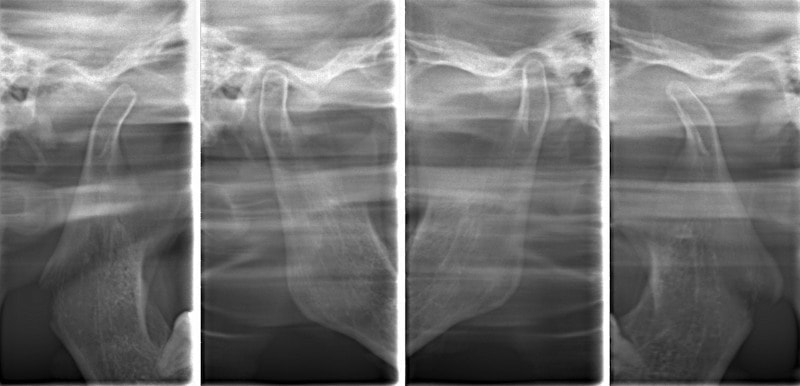

顎関節レントゲン分析

反対咬合の方はやはり下顎肢が細い傾向にあります。

顎位は良好な状態です。